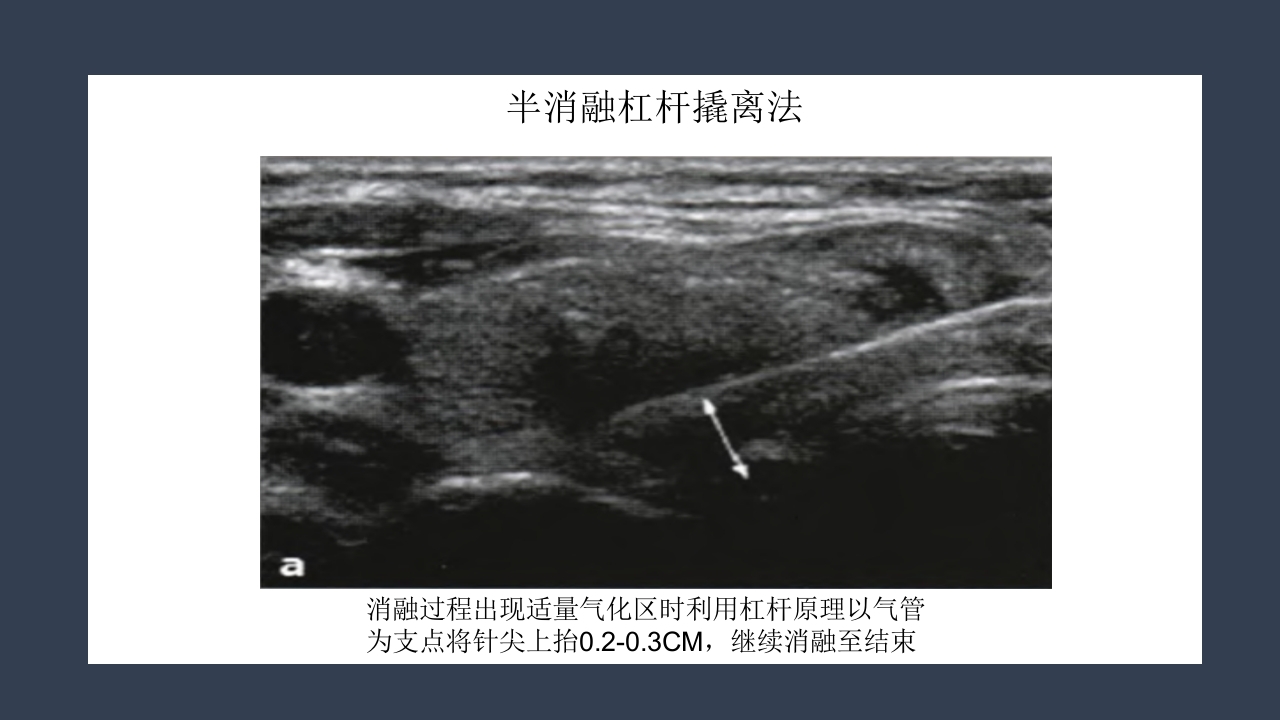

超声引导下甲状 腺结节射频消融 汇报人:xxx 时间:20XX年XX月 研究背景 甲状腺结节的患病率 尸体解剖:50.5% 人群普查可触及:3%-6% 超声发现非触及:20%-60% 男女比可达到1:4 甲状腺良性结节也有恶变可能 研究背景 Benign 甲状腺 结节 Malignant 5%-15% 2%恶性由 良性转变而 来 甲状腺结节的治疗方法 治 疗 传统手术切除 腔镜下切除 微创消融 甲状腺叶 全切除 次全切除 胸骨切迹 锁骨下 胸骨前乳晕 腋窝等 无水 乙醇 硬化 放射性 碘131植入 射频消融 微波消融 激光消融 传统手术切除 6-8CM的手术瘢痕 腔镜下切除 手术时间长,剥离面大,术后 疼痛强,是创伤较大的手术。 射频消融术 RFA治疗甲状腺结节的优势 ①微创或无创治疗技术是医学发展的大趋势。 ②...